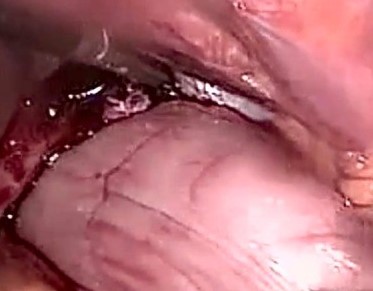

Diaphragmatic hernia before and after reduction of the stomach (Courtesy Dr. V. Penopoulos)